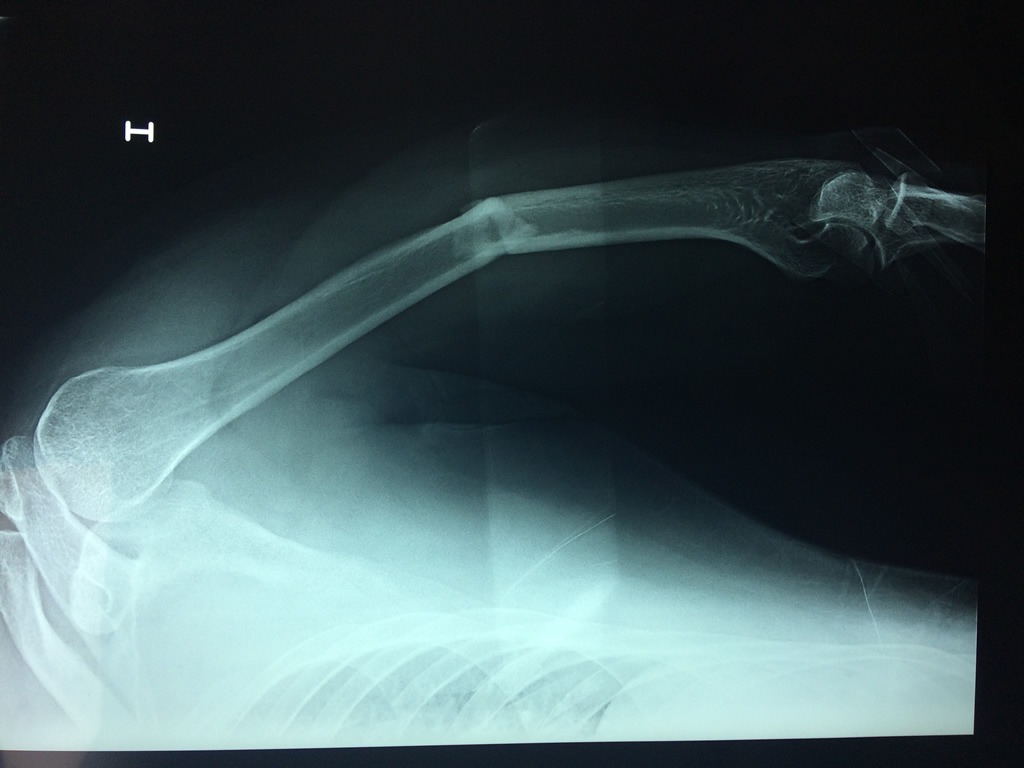

humeroEl Húmero (en latín, humerus) es el hueso más largo de las extremidades superiores en el ser humano. ​ Forma parte del esqueleto apendicular superior y está ubicado en la región del brazo. ... El extremo proximal del húmero tiene la cabeza, cuellos quirúrgico y anatómico y tubérculos mayor y menor.

Húmero